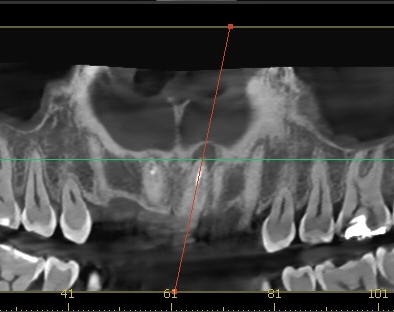

엑스레이 검사 결과, 뿌리 끝에는 염증도 생겨 있었습니다.

단순히 겉모습의 문제만이 아니라, 치아 뿌리 쪽도 치료가 필요했던 상황이었습니다.

치료는 재신경치료와 BOPT컨셉을 이용한 크라운 재치료로 계획했습니다.

25.08.11

25.08.11 기존 크라운 제거 후 모습